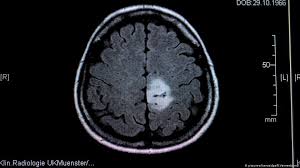

When you have a child with cancer, social media can provide a wonderful lifeline of support. Having your child diagnosed with a terminal brain tumour is one of the most devastating and terrifying things that can happen to any parent. If the tumor affects the optic pathway, which is responsible for sight, the child may experience vision changes. A seizure is sometimes the first sign of a brain tumor, but it can happen at any stage. This is partly because pressure in the brain increases when you're lying down, and a tumor can make that worse. Children of any age may be affected. When claire was sick i used caring bridge to communicate updates to the myriads of supportive people who were following her story throughout treatment. This way you will be able to address questions that your child may have about your cancer diagnosis. Brain tumors, either malignant or benign, are tumors that originate in the cells of the brain. Many children with a brain tumor experience headaches before their diagnosis. For most children, you do not need to go into a lot of detail about side effects. There are new and better drugs and treatments, and we can now also work. As the tumor grows, it creates pressure on and changes the function of surrounding brain tissue, which causes signs and symptoms such as headaches, nausea and balance problems.

A seizure is sometimes the first sign of a brain tumor, but it can happen at any stage. Usually, symptoms like a headache or confusion are just your body's way of telling you to hydrate or sleep more. For children with common headaches, a red flag that it might be something more serious than a simple migraine would be if the headaches continued to get worse over time, becoming either more severe or more frequent. The guiding principle should be to tell the truth in a way that children are able to understand and prepare themselves for the changes that will happen in the family. The cause of most brain tumours is unknown, but there are several risk factors that may increase your chances of developing a brain tumour.

About 400 children in the uk develop brain tumours each year. More children than ever are surviving childhood cancer. We know that medications that treat brain tumors in one site can also get to other sites of the brain. If your child has been diagnosed with a brain tumor, memorial sloan kettering is ready to help. For example, you might tell a child, grandma has to take very strong medicine to get rid of the cancer. A benign tumor does not contain cancer cells and usually, once removed, does not recur. I know many have also used facebook to do the same. Children of any age may be affected. A ct (computed tomography) scan , mri (magnetic resonance imaging , or possibly both. Key points about a brain tumor in a child. In some children, seizures are the first symptom of a brain tumor. If you ever have concerns about symptoms your child is having, talk with your child's doctor right away. 5 brain tumors might also cause other neurological symptoms, such as trouble walking, seizures or sudden changes in their personality.